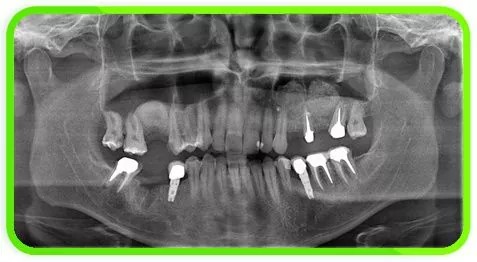

• Не всем пациентам удается произвести имплантацию зубов, ввиду отсутствия достаточного объема костной ткани. После удаления зуба прекращается нагрузка на данный участок альвеолярного отростка в процессе жевания, что приводит к рассасыванию костной ткани.

Чем дольше отсутствует нагрузка, тем более выраженный дефицит объема кости. В конечном итоге толщина и высота кости альвеолярного отростка уменьшаются настолько, что произвести постановку имплантатов с последующим изготовлением несъемного протеза не представляется возможным.

Выбор методики костной пластики определяется только после анализа компьютерной томографии. КТ позволяет оценить объем костной ткани во всех направлениях, а также определить плотность костной ткани.